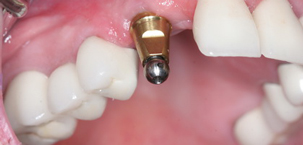

Top Class Treatment

All Types Dental Services